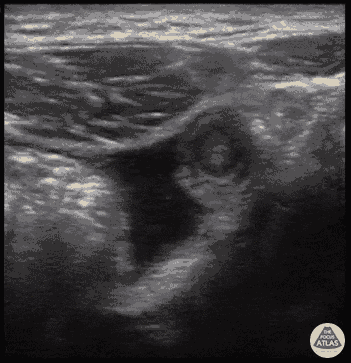

Abnormal appendix measuring 8 mm in diameter in transverse view surrounded by free fluid, consistent with appendicitis.